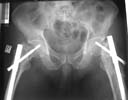

Attached here few x-rays of a multi-trauma patient. He is a 51years old man,sustain MVA at 08/15/99 and refer to our hospital few days ago, more than twoweeks after injury. He sustain Bilateral femoral fracture including femoralneck, A right humerus fracture, right distal radius fx, left open ulnar fx,right tibial plateau (type III) fx and Chopart fracture dislocation of the rightfoot. At the other hospital where he was admitted, He underwent laparotomy andfixation of both femur by reconstruction IMN, application of Ex Fix to thehumerus, and reduction and K.W. fixation of the Rt foot. He is currently stable and conscious. He is scheduled next week for replacing of the Rt IMN to aretrograde nail and pinning (6.5 mm screws) of the neck fracture, fixation ofthe ulna, distal radius and tibial plateau.

AP Pelvis

Lt femur

Rt femur

The implant selection was right but application technique and length of the nail were not. Lateral x-rays of the hip should be taken to confirm reduction of the femoral neck (bilaterally?).

In my opinion both fractures sould be revised with closed interlocking nailing with the same nail, appropriate length using two proximal locking screws to the head. Two screws for distal locking must be also used because these are very unstable fractures.

Lt hip

Rt hip